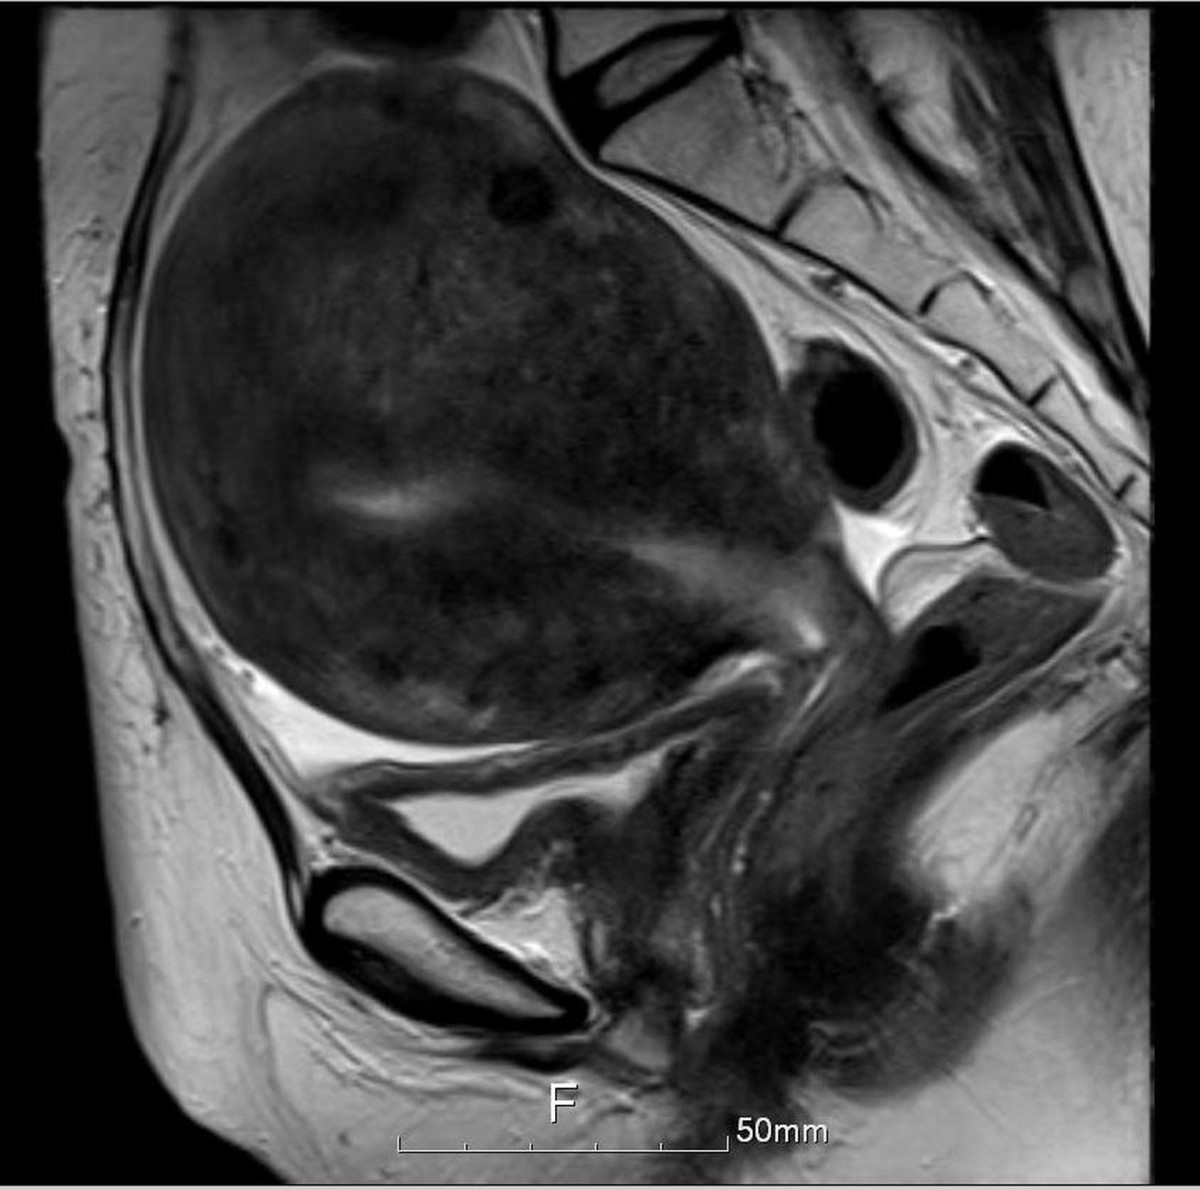

Figure 3

Pelvic MRI after concurrent chemoradiation therapy and HT-guided SBRT shows multiple uterine myomas and adenomyosis without local recurrence or pelvic lymphadenopathy.